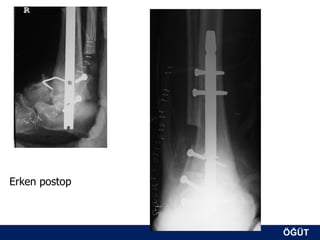

Erken postop

OLGU No 2   S.S., 55y, K